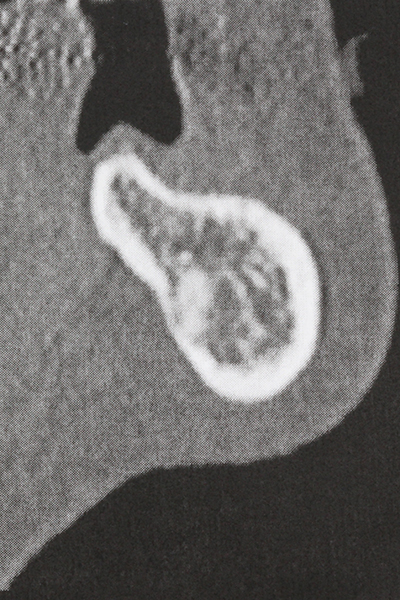

Preparation of the lateral window during an external sinus floor elevation is challenging, particularly for implantologists with little surgical experience. Removal of the bone cover of the sinus without injuring the underlying Schneiderian membrane is only part of the operation – after establishing an adequate access, the membranous lining of the sinus must be carefully mobilized to make space for the augmentation materials or the implants. Piezo surgery is useful for this indication in two ways: diamond-coated instruments can be used for selective bone ablation and the underlying mucous membrane remains intact when the procedure is done carefully. The ultrasonic frequencies also enable detachment of the mucous membrane without complications – the frequencies are transmitted into the space between the mucous membrane and sinus floor by special blunt attachments (Cassetta, Ricci et al. 2012, Pereira, Gealh et al. 2014) (Rickert, Vissink et al. 2013). As a result, it is not surprising that current reviews of external sinus floor elevation positively evaluate the use of piezoelectric devices as well as the use of roughened implant surfaces and bone replacement materials (Wallace, Tarnow et al. 2012).

Indication: Sinus lift